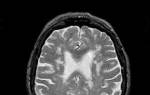

Врачи отмечают, что диагностика ангиом головного мозга, таких как кавернозные и венозные, требует комплексного подхода. На первом этапе важна магнитно-резонансная томография, которая позволяет точно визуализировать образование и оценить его размеры и расположение. Специалисты подчеркивают, что правильная интерпретация снимков играет ключевую роль в выборе метода лечения.

Лечение и диагностика ангиом головного мозга, таких как кавернозные и венозные, вызывают много обсуждений среди пациентов и специалистов. Многие люди отмечают, что ранняя диагностика играет ключевую роль в успешном лечении. Современные методы визуализации, такие как МРТ и КТ, позволяют точно определить расположение и размер ангиомы, что значительно облегчает выбор тактики лечения.

Перед тем как направить пациента на операцию, врачи проводят комплексные диагностические исследования, которые включают сбор анамнеза, ангиографию и компьютерную томографию. Если обнаруживаются каверны, то применяется МРТ-диагностика.

Регулярно проходите обследования, такие как МРТ или КТ, для мониторинга состояния ангиомы. Это поможет выявить изменения в ее размере или структуре и своевременно принять меры, если это необходимо.